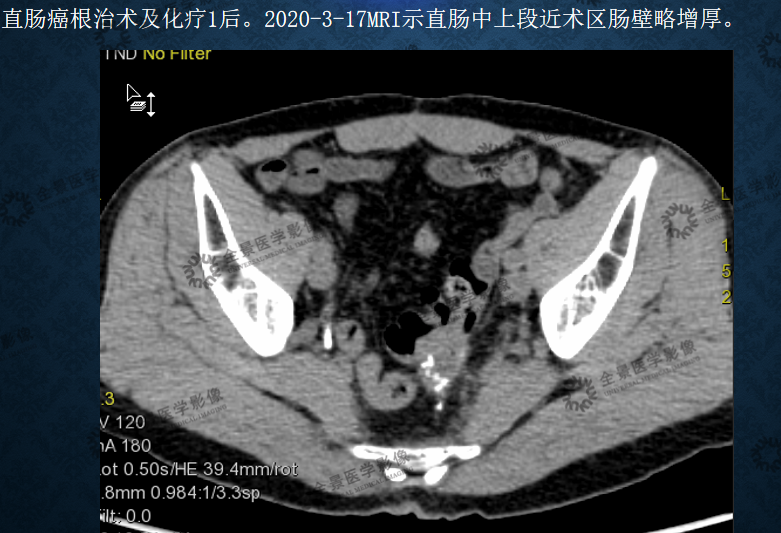

(3)疗效对比